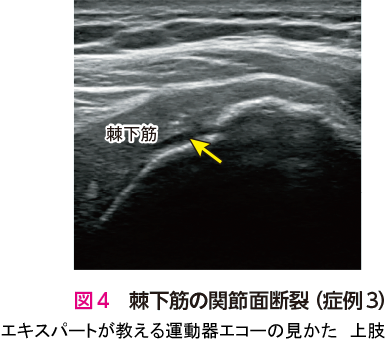

エキスパートが教える運動器エコーの見かた 上肢〜診療の鍵と, エキスパートが教える運動器エコーの見かた 上肢〜診療の鍵と,

エキスパートが教える運動器エコーの見かた 上肢〜診療の鍵と, 61cr4eo2EWL._AC_UF350,,

運動器エコーを用いた 足の診かた | 日本医事新報社 Web, エキスパートが教える運動器エコーの見かた 上肢〜診療の鍵と「エキスパートが教える運動器エコーの見かた 上肢 下肢」中島 祐子 / 中瀬 順介定価: ¥ 7000#中島祐子 #中島_祐子 #中瀬順介 #中瀬_順介 #本 #自然/医療・薬学・健康上下肢セット販売になります。定価 ¥7.700 2点で¥15.400の商品本商品は【裁断済み】のため状態を悪いにしてあります。細かな点では折れなどありません。またマーカーや書き込みもありません。綺麗にスキャンできる状態になります。「エキスパートが教える運動器エコーの見かた 上肢」中島 祐子 / 中瀬 順介「エキスパートが教える運動器エコーの見かた 下肢」中島 祐子 / 中瀬 順介#運動器エコー#エコー#エコー検査